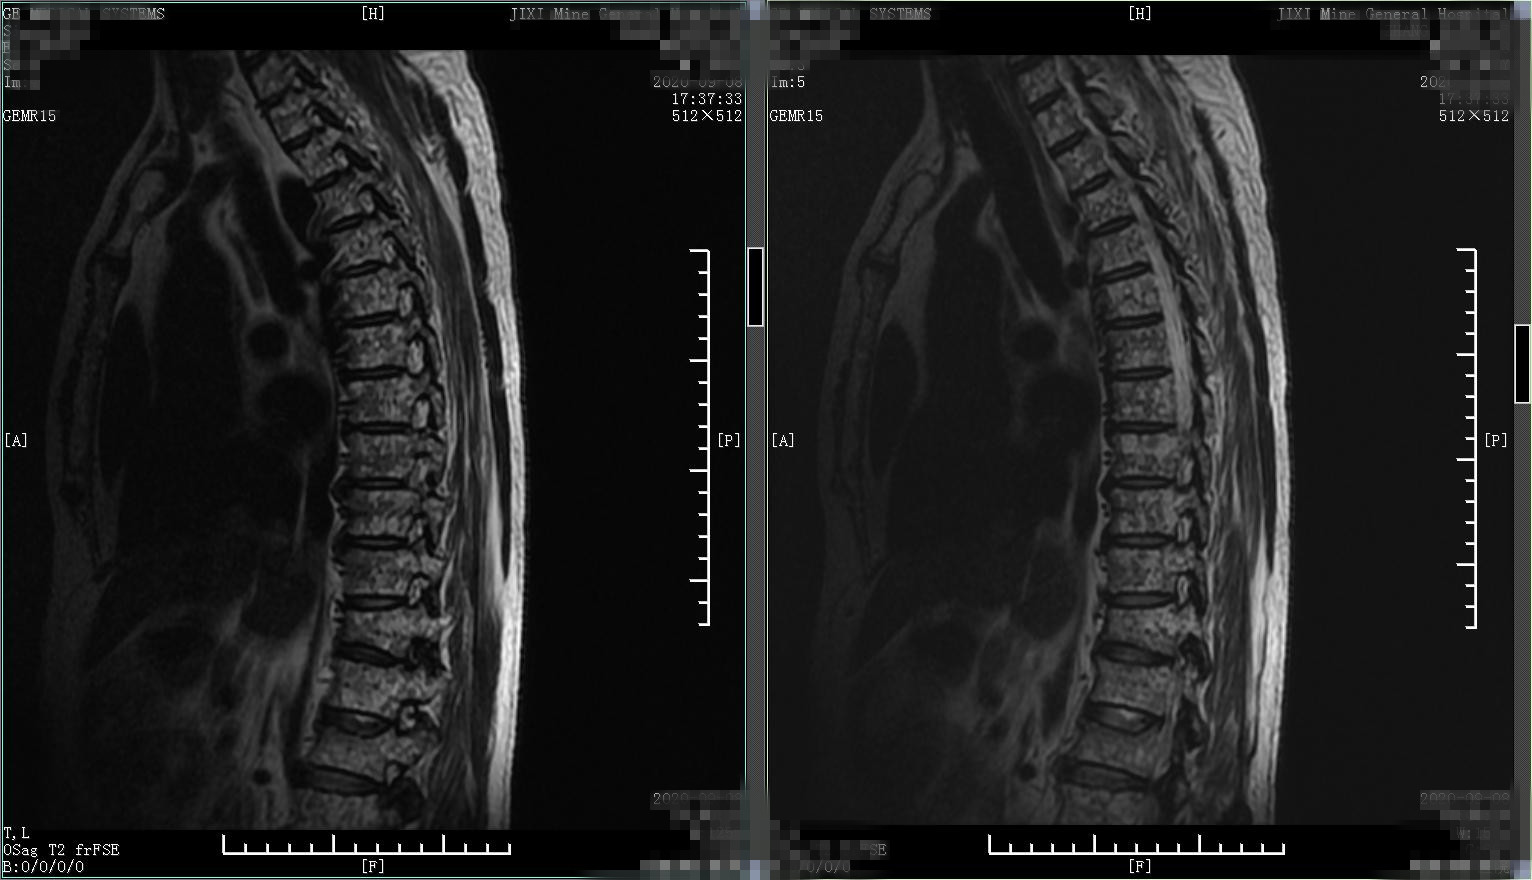

患者1、男性、57岁,病人就诊前2个月逐渐出现腰背部疼痛进行性加重,无外伤史,自行外贴膏药、口服活血化瘀药物、热敷治疗,起初症状略减轻,但1个月后逐渐出现疼痛加剧,变换体位及活动均明显收到影响,夜间常自感低热,半夜常被疼醒。查腰椎X线片,发现腰1、胸12椎体轻度变扁,骨质疏松,疼痛是什么原因,难道是骨质疏松导致的椎体压缩性骨折?所以进一步又查胸腰椎核磁,结果如下,椎体弥漫性异常信号改变,胸12、腰1椎体病理性骨折。

椎体多发异常信号

椎体多发异常信号,胸12、腰1椎体骨折